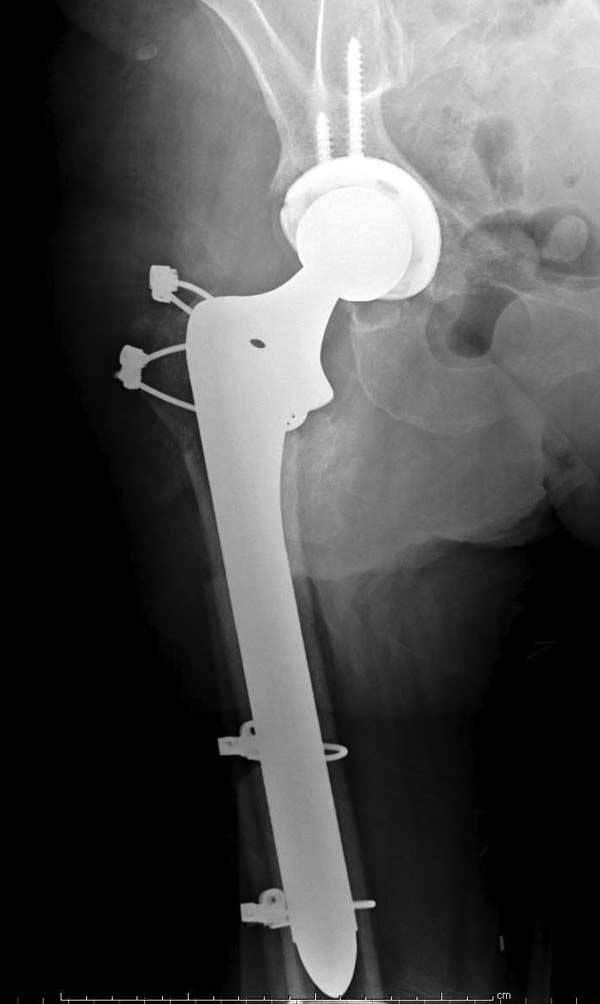

Третья операция-продолжения усилии "синьорами пэрами" по разрушению нормальной анатомии. Крест на головку! По видимому возраст позволяет биполярную конструкции, и при дефекте  calcar пошли на обычный цементный. Ягодичные мышцы потеряли связь с вертелом, т.е. отсутствует верхний удержатель, и результат “a Big Screw Up!” Снимки вызывают головокружение!

Такие “чужие осложнения” встречаются у всех и представляю банальный случай, который шаг за шагом показано как перерос в более сложный процесс... Больная 70 лет, множественные ко-морбидности, чрезвертельный перелом первоначально фиксирован Гамма 3. Осложнение в течение 6 недель, ревизия тотальной артропластикой и во время установки ножки обнаружена трещина диафиза (17), из малого доступа фиксация алло-графтом.

Имя     : 19 hip PO final.jpg

Тип     : image/jpg

Размер  : 48504 байтов

Описание: отсутствует

Url     : http://weborto.net:8080/pipermail/ortho/attachments/20120509/52aada75/attachment-0042.jpg